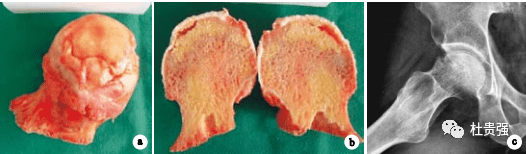

股骨头坏死时呈顶部半月状软骨下断裂,股骨头软骨下骨小梁与软骨分离,X线表现在骨性关节面的下方出现了2-4mm宽的新月形透明带,即“新月征“,又称“半月征”。

新月征是 位于未被修复坏死松质骨区软骨下骨板下,于骨折后再骨折线下形成的空腔, 开始于股骨头外侧已修复坏死骨、未被修复坏死骨和软骨下骨板三者交界处的软骨下骨板的局灶性骨吸收,局灶性吸收在软骨下骨板产生裂隙,裂隙的产生造成在裂隙周围的应力集中,集中的应力累积在软骨下骨板和未被修复坏死松质骨交界处造成二者交界处的骨折。裂隙的产生也同时为骨髓内空隙水的外流提供了通道,在功能荷载的作用下,存在于未被修复坏死松质骨骨架内的孔隙水被逐渐挤出,引起施加在未被修复坏死松质骨骨架上有效应力增加。当有效应力超过未被修复坏死松质骨骨架的力学强度时,未被修复坏死松质骨骨架被压缩和体积减小,导致软骨下骨板的新月形空腔形成,在X线片上显示新月征。

新月征的出现是股骨头坏死塌陷的标志,对应为ARCOIIIa期。

这是保髋治疗的最后的时机,失去这个时机保髋的成功率就很低了。

但出现新月征后就一定丧失了保髋的机会吗,回答是NO!